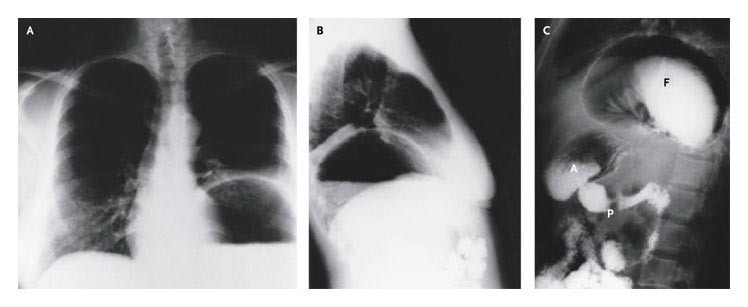

Posteroanterior and lateral chest radiography revealed a large intrathoracic gastric bubble (Panels A and B), and a barium-contrast study of the upper gastrointestinal tract confirmed the presence of a large paraesophageal hernia (Panel C). A denotes gastric antrum, F gastric fundus, and P pylorus.